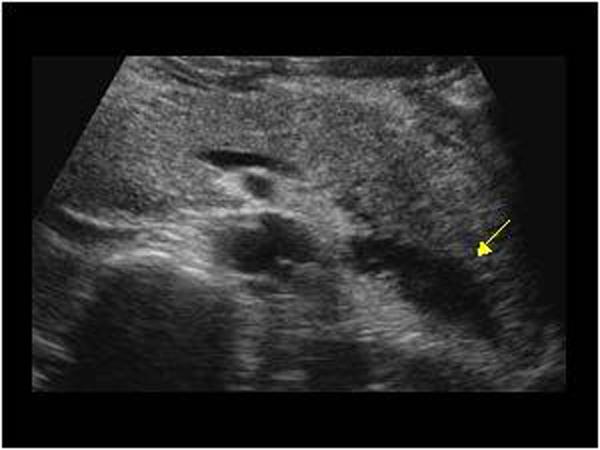

Pancreatic Psydocyst

Spherical fluid collection of pancreatic enzymes that arise from inflamatory, necrotic and hemorrhage processes of the pancrreas

persistently elevated amylase and lipase

Pancreatic Psydocyst

Spherical fluid collection of pancreatic enzymes that arise from inflamatory, necrotic and hemorrhage processes of the pancrreas

persistently elevated amylase and lipase

Pancreatic Psydocyst

Spherical fluid collection of pancreatic enzymes that arise from inflamatory, necrotic and hemorrhage processes of the pancrreas